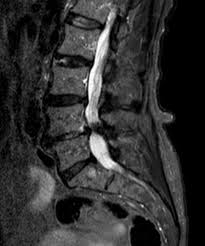

Stenosi del Canale Lombare

Cos’è

La stenosi lombare è un restringimento del canale vertebrale o dei forami da cui escono i nervi spinali.

Il restringimento può comprimere i nervi e causare:

- Dolore o crampi alle gambe

- Intorpidimento e debolezza muscolare

- Peggioramento dei sintomi durante la camminata (claudicatio neurogena)

- Sollievo quando ci si siede o ci si piega in avanti

Cause

La causa più comune è la degenerazione delle strutture spinali: osteofiti (escrescenze ossee), ispessimento dei legamenti o protrusioni discali.